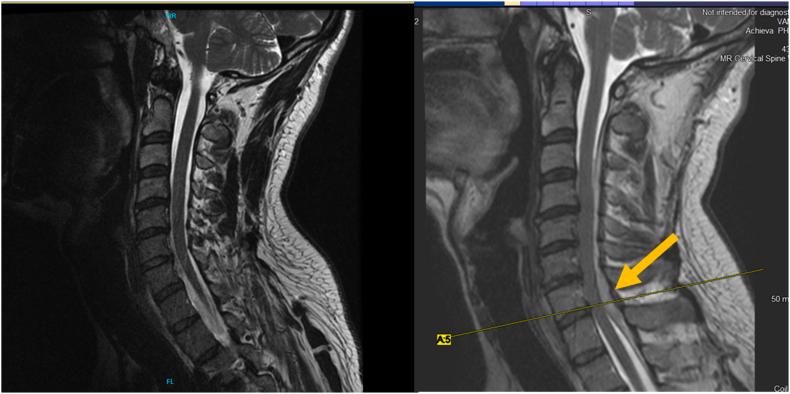

Posterior internal vertebral venous plexus, the "Black Ice" of epidural hematoma: A letter to the editor.

Posterior internal vertebral venous plexus, the "Black Ice" of epidural hematoma: A letter to the editor.椎内静脉后丛,硬膜外血肿的“黑冰”:致编辑的一封信

Fulminant Cervical Epidural Hematomas: Why Do They Happen, How Can We Minimize Their Occurrence, and What Can We Do When They Do Occur? A Perspective.

Spinal Epidural Hematoma after Interlaminar Cervical Epidural Steroid Injection.

Cervical epidural hematoma following interlaminar epidural steroid injection via the contralateral oblique view in patient taking omega-3 fatty acids.患者服用欧米伽-3 脂肪酸后,从对侧斜位行椎间孔硬膜外类固醇注射导致颈椎硬膜外血肿。